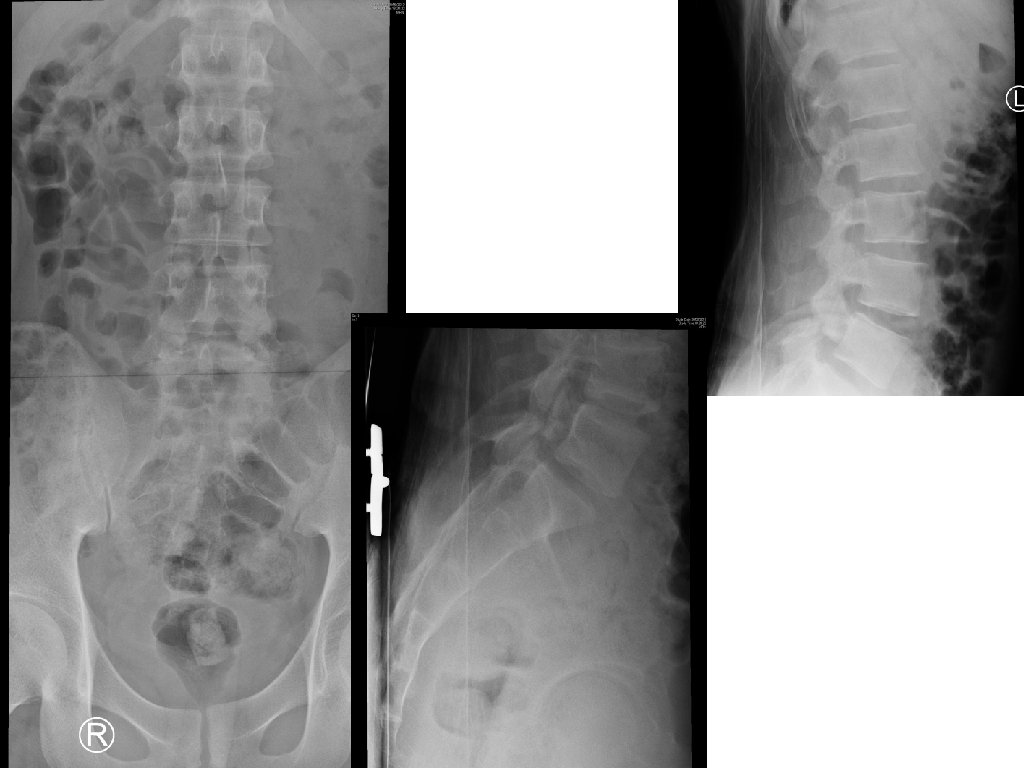

Case 2 • A 20 year-old badminton player presented with low back pain after landing from a jump during a ball game. He was so painful that he could not walk. • There was no bony tenderness and no lower limb neurological deficit. • X-ray LS spine was done.

Case 2 - Questions 1. What is the X-ray abnormality? 2. What is the view of the second set of X-ray? 3. To assess the stability of his lumbar spine, what additional view of x-ray can be ordered? 4. Name two likely causes of this x-ray condition in our patient? 5. What is the management?